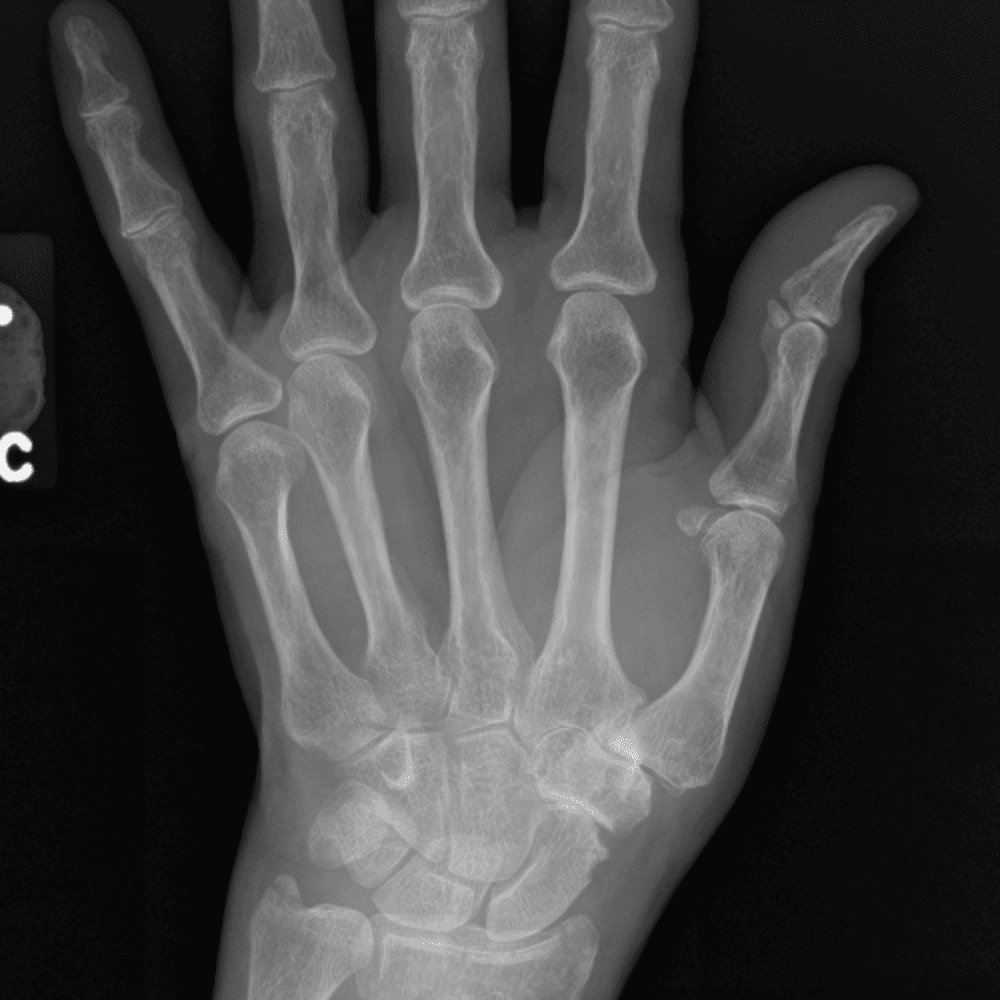

Simuliert den Dienst durch subtile oder schwierige Fälle und einige Normalbefunde.

30 Fälle